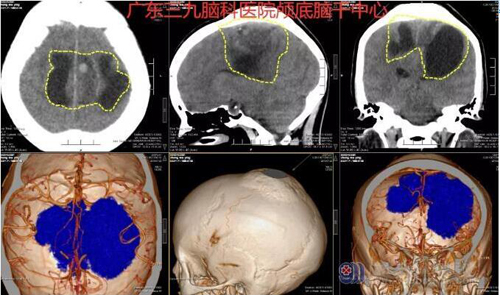

神经外科门诊医生张良看了郑女士的情况,建议去做头颅影像检查看看头部是否有异常,结果显示:额顶部窦镰旁两侧囊实性占位性病变,范围约8.6×6.6×6.3cm,考虑为中央区上矢状窦镰旁脑膜瘤。

图1:术前CTA示额顶部窦镰旁两侧囊实性占位性病变,范围约8.6×6.6×6.3cm,病变实性部分内示多发细小血管影,邻近上矢状窦中断,邻近颅骨增厚。